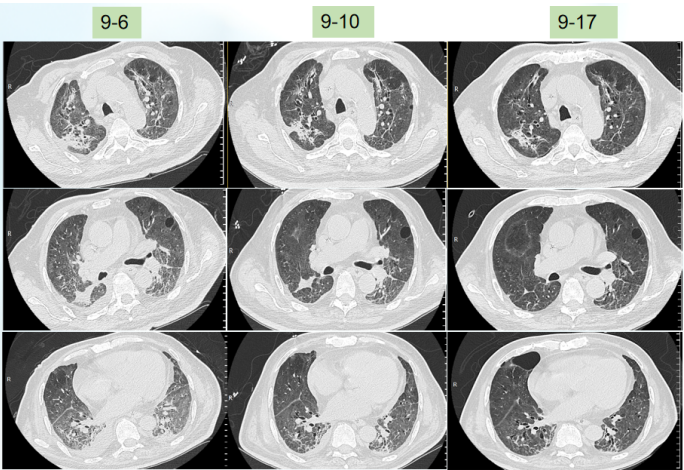

患者入科后体温相对正常,但在7月23日体温升高,考虑当时予以大剂量激素治疗,以及患者肺部病变情况,故在原有抗感染基础上加用了磺胺类药物(图2)。图2  患者体温及感染指标变化趋势(7月19-25日)胸部CT:7月23日在ECMO支持下复查患者胸部CT,发现感染较前加重(图3)。

根据上述病原学结果,在7月28日患者出现发热后,考虑鲍曼不动杆菌感染可能性大,遂加用替加环素,患者体温下降,但至7月30日,患者体温再次升高,白细胞计数逐渐升高。结合气管镜和mNGS回报结果,考虑此时可能出现肺炎克雷伯菌感染,遂加用头孢他啶阿维巴坦,患者体温逐渐下降。8月4日ECMO撤机。患者撤离ECMO后,体温再次升高,考虑鲍曼不动杆菌感染,在原治疗方案基础上加用头孢哌酮舒巴坦(图7)。图7  患者体温及感染指标变化趋势(7月26日-8月8日)撤离ECMO后,复查患者胸部CT可见肺部病变控制较好,但8月27日发现患者肺部出现新的感染(图8)。加用头孢他啶阿维巴坦和头孢哌酮舒巴坦后,白细胞呈下降趋势,但患者体温仍不稳定,时有波动,遂联用多黏菌素(雾化),此后,患者白细胞逐渐趋于正常(图9)。图9  患者体温及白细胞计数变化趋势(8月9-22日)治疗回顾